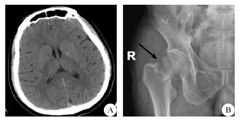

患者男性,57岁,既往体健,于2017年2月18日因"脑梗死"收入解放军第三一三医院神经内科。入院前2 h无明显诱因突然头晕后摔倒,右下肢疼痛不适,同时患者家属发现其出现言语不清、不识家人、右侧肢体活动障碍。入院体检:神清,定向力、理解力、计算力障碍,言语不清,额纹对称,右侧鼻唇沟变浅,伸舌不偏;右上肢肌力2级,肌张力正常,右侧肢体痛温觉减退,四肢腱反射对称存在,右侧巴氏征可疑;颈软,克氏征及布氏征阴性,余神经系统体检不合作;右下肢活动受限,外旋畸形,右髋关节压痛。入院后查头颅CT平扫未见异常(图1A),骨盆正位片提示右侧股骨颈骨折(图1B)。查血常规、肝肾功能、凝血功能、离子,均正常。美国国立卫生研究院卒中量表(National Institute of Health stroke scale,NIHSS)评分15分。患者家属强烈要求溶栓治疗,请我院骨科会诊评估后考虑骨折处大量出血可能性不大,遂向患者家属交待溶栓风险并征得其同意后,于发病3.5 h予rt-PA 0.9 mg/kg静脉溶栓,溶栓后患者右侧肢体活动好转(右上肢肌力4级),定向力、理解力基本正常,仍言语不清,NIHSS评分4分。溶栓全过程患者无头痛、出血,右侧髋关节处未见淤血。溶栓24 h复查颅脑CT未见出血、复查髋关节CT未见明显出血(图2)。发病1 d后查MRI证实左侧额颞叶多处新发梗死灶(图3)。溶栓2周后转至我院骨科行右髋关节置换术,手术效果满意。随访3个月,患者言语基本正常,右侧肢体活动可,跛行,改良Rankin量表评分2分。

A:入院时颅脑CT未见明显异常;B:入院时骨盆正位X片提示患者右侧股骨颈骨折(箭头所示)